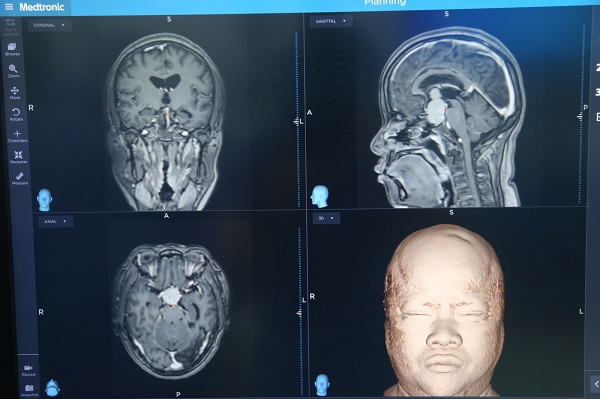

Hình ảnh khối u tuyến yên khổng lồ ở người bệnh - Ảnh: VGP/TM